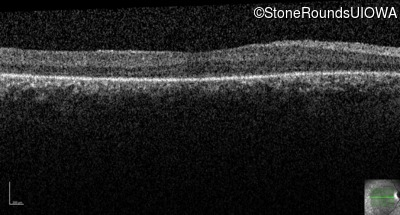

Age at visit: 12 years

Age at visit: 13 years

Age at visit: 15 years

Age at visit: 17 years

Age at visit: 19 years